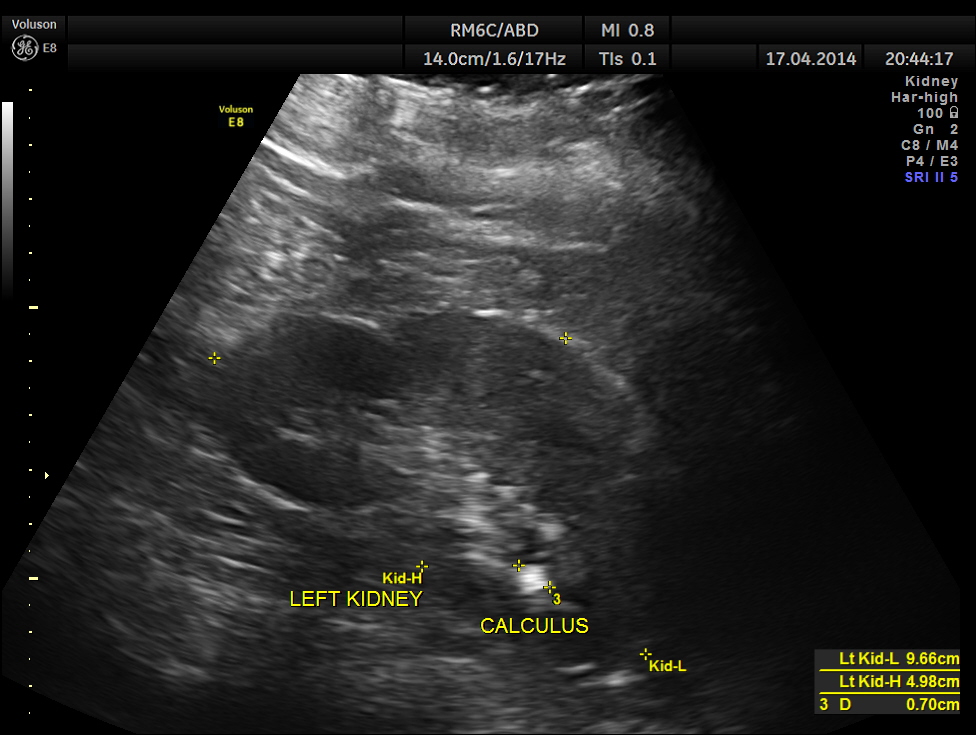

The ultrasound gave us a few inconclusive findings . Uterus was massively enlarged ; a large fibroid was seen ; adenomyosis was seen ; endometrium was thickened ; two large mass lesions were seen in the right upper quadrant and right lumbar region . But it was difficult to ascertain the origin of these extra uterine masses .